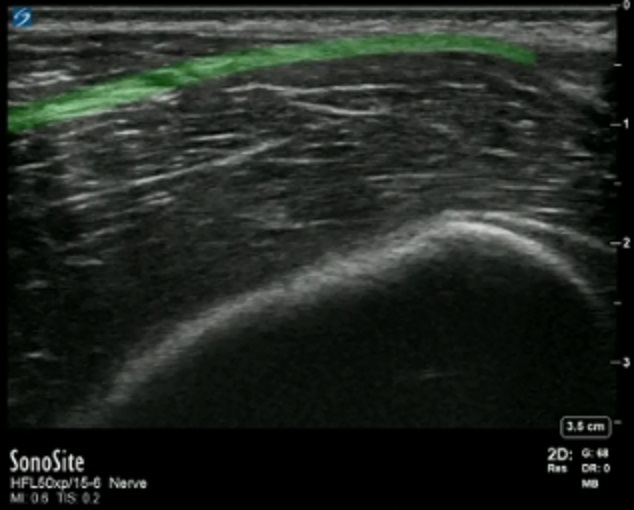

腸骨筋膜平面の強調

左側: 頭蓋

右側: 尾側

強調表示された領域: 腸骨筋膜平面